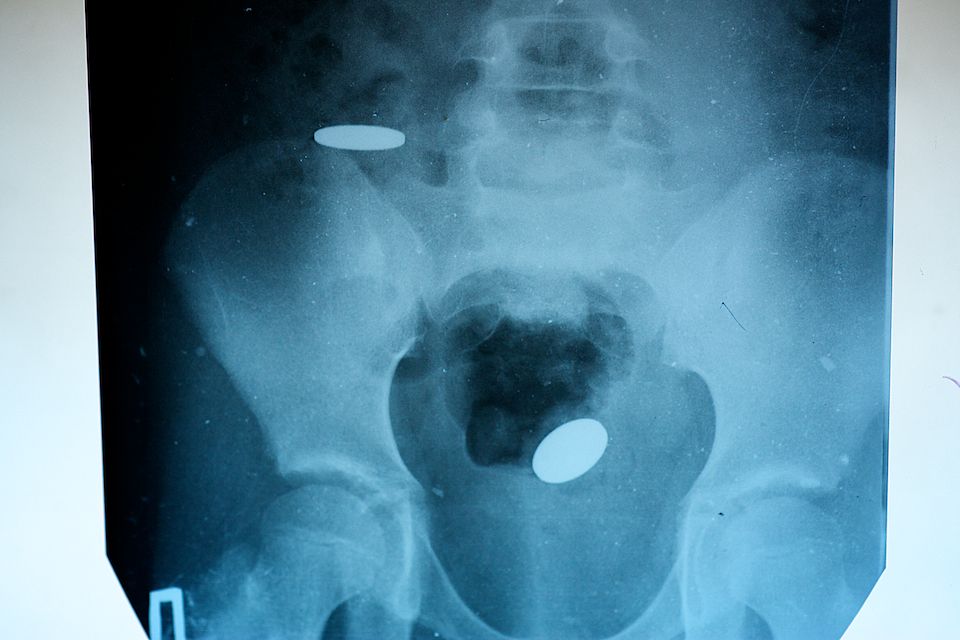

Проглоченные монетки, к сожалению, не всегда выходят сами. Это объясняется размерами и особенностью строения кишечника ребенка. Монетки так же могут вызвать непроходимость, воспаление и перфорацию

Магниты, несмотря на округлую форму и небольшой размер, представляют для ребенка огромную опасность именно из-за своих магнитных свойств. Попав в разные отделы кишечника, магниты притягиваются друг другу так, что в месте притяжения ткань отмирает и кишечник перфорируется. Опасен даже один проглоченный магнит, потому что может притягиваться к металлическим элементам одежды, например, к пряжке ремня. Хирурги сравнивают вред, причиненный проглоченными магнитами с огнестрельным ранением – полостная операция, ушивание кишечника, перитонит (воспаление брюшной полости)

А это снимок трехлетней Пейтон Бушнелл, которая проглотила 37 магнитных шариков Buckyball. Родители девочки решили, что у ребенка болит живот, однако рентгеновский снимок продемонстрировал замкнутое ожерелье Buckyball в кишечнике маленькой девочки.